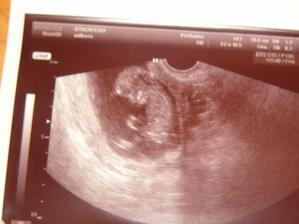

18.12.2009 sme sa dozvedeli ze cakame druhe babulko. na uzv som ho prvy krat videla a meralo 5milimetrov...